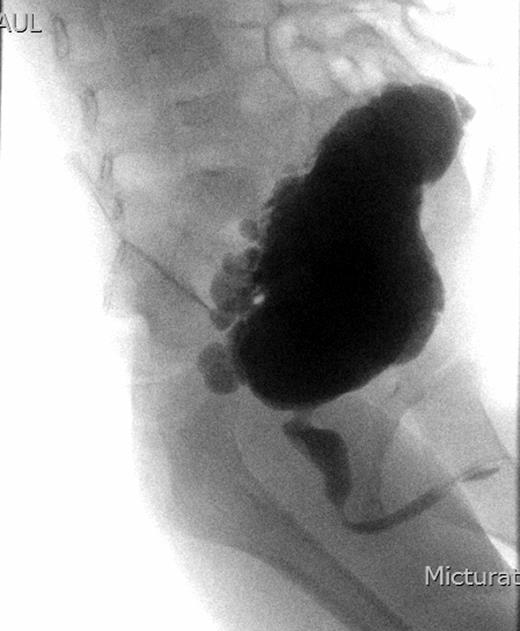

Subsequently, a Micturating Cystourethrogram (MCUG) was reported to show a markedly trabeculated bladder and posterior urethral valves (PUVs) (see Fig. 2). The child was also found to have deranged renal function (urea 21.7, cretainine 148). His blood pressure remained high despite the commencement of oral Nifedipine twice daily.

An urgent MCUG showing a markedly trabeculated bladder with dilatation of the posterior urethra.

With problems controlling blood pressure and worsening renal function (urea 25.5 and creatinine 188), the child was transferred to Urologists, who performed an urgent cystoscopy for posterior urethral valve (PUV) and/or stricture formation as the result of catheterization during stage-1 correction surgery of Hypospadias. Cystoscopy identified a PUV, which was resected. On removal of the catheter, the patient's renal function deteriorated rather than showing the anticipated improvement. Re-cystoscopy was undertaken upon which the identification of an anterior urethral valve (AUV) was made, which was resected. Even on retrospective review of the MCUG, AUV could not be identified; this could possibly be due to the poor urinary flow as a result of the PUV, as well as the catheter in situ obscuring visualization.